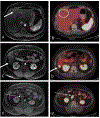

Figures